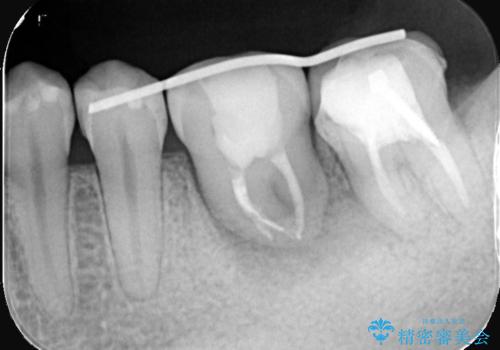

- 主訴:左下6番目の歯の周りが痛くなり、他院で診てもらったが抜歯と言われてしまった。ネットで歯牙移植というものを知りやっている医院を探している。

左下6番目の歯の周りに大きく透過像を認め、再根管治療後の予後が良くない可能性が大きく当院でも抜歯適用歯と説明しました。欠損部に対しインプラント治療や歯牙移植(左下の親知らずの移植)、ブリッジを提案し、歯牙移植を行うこととなりました。